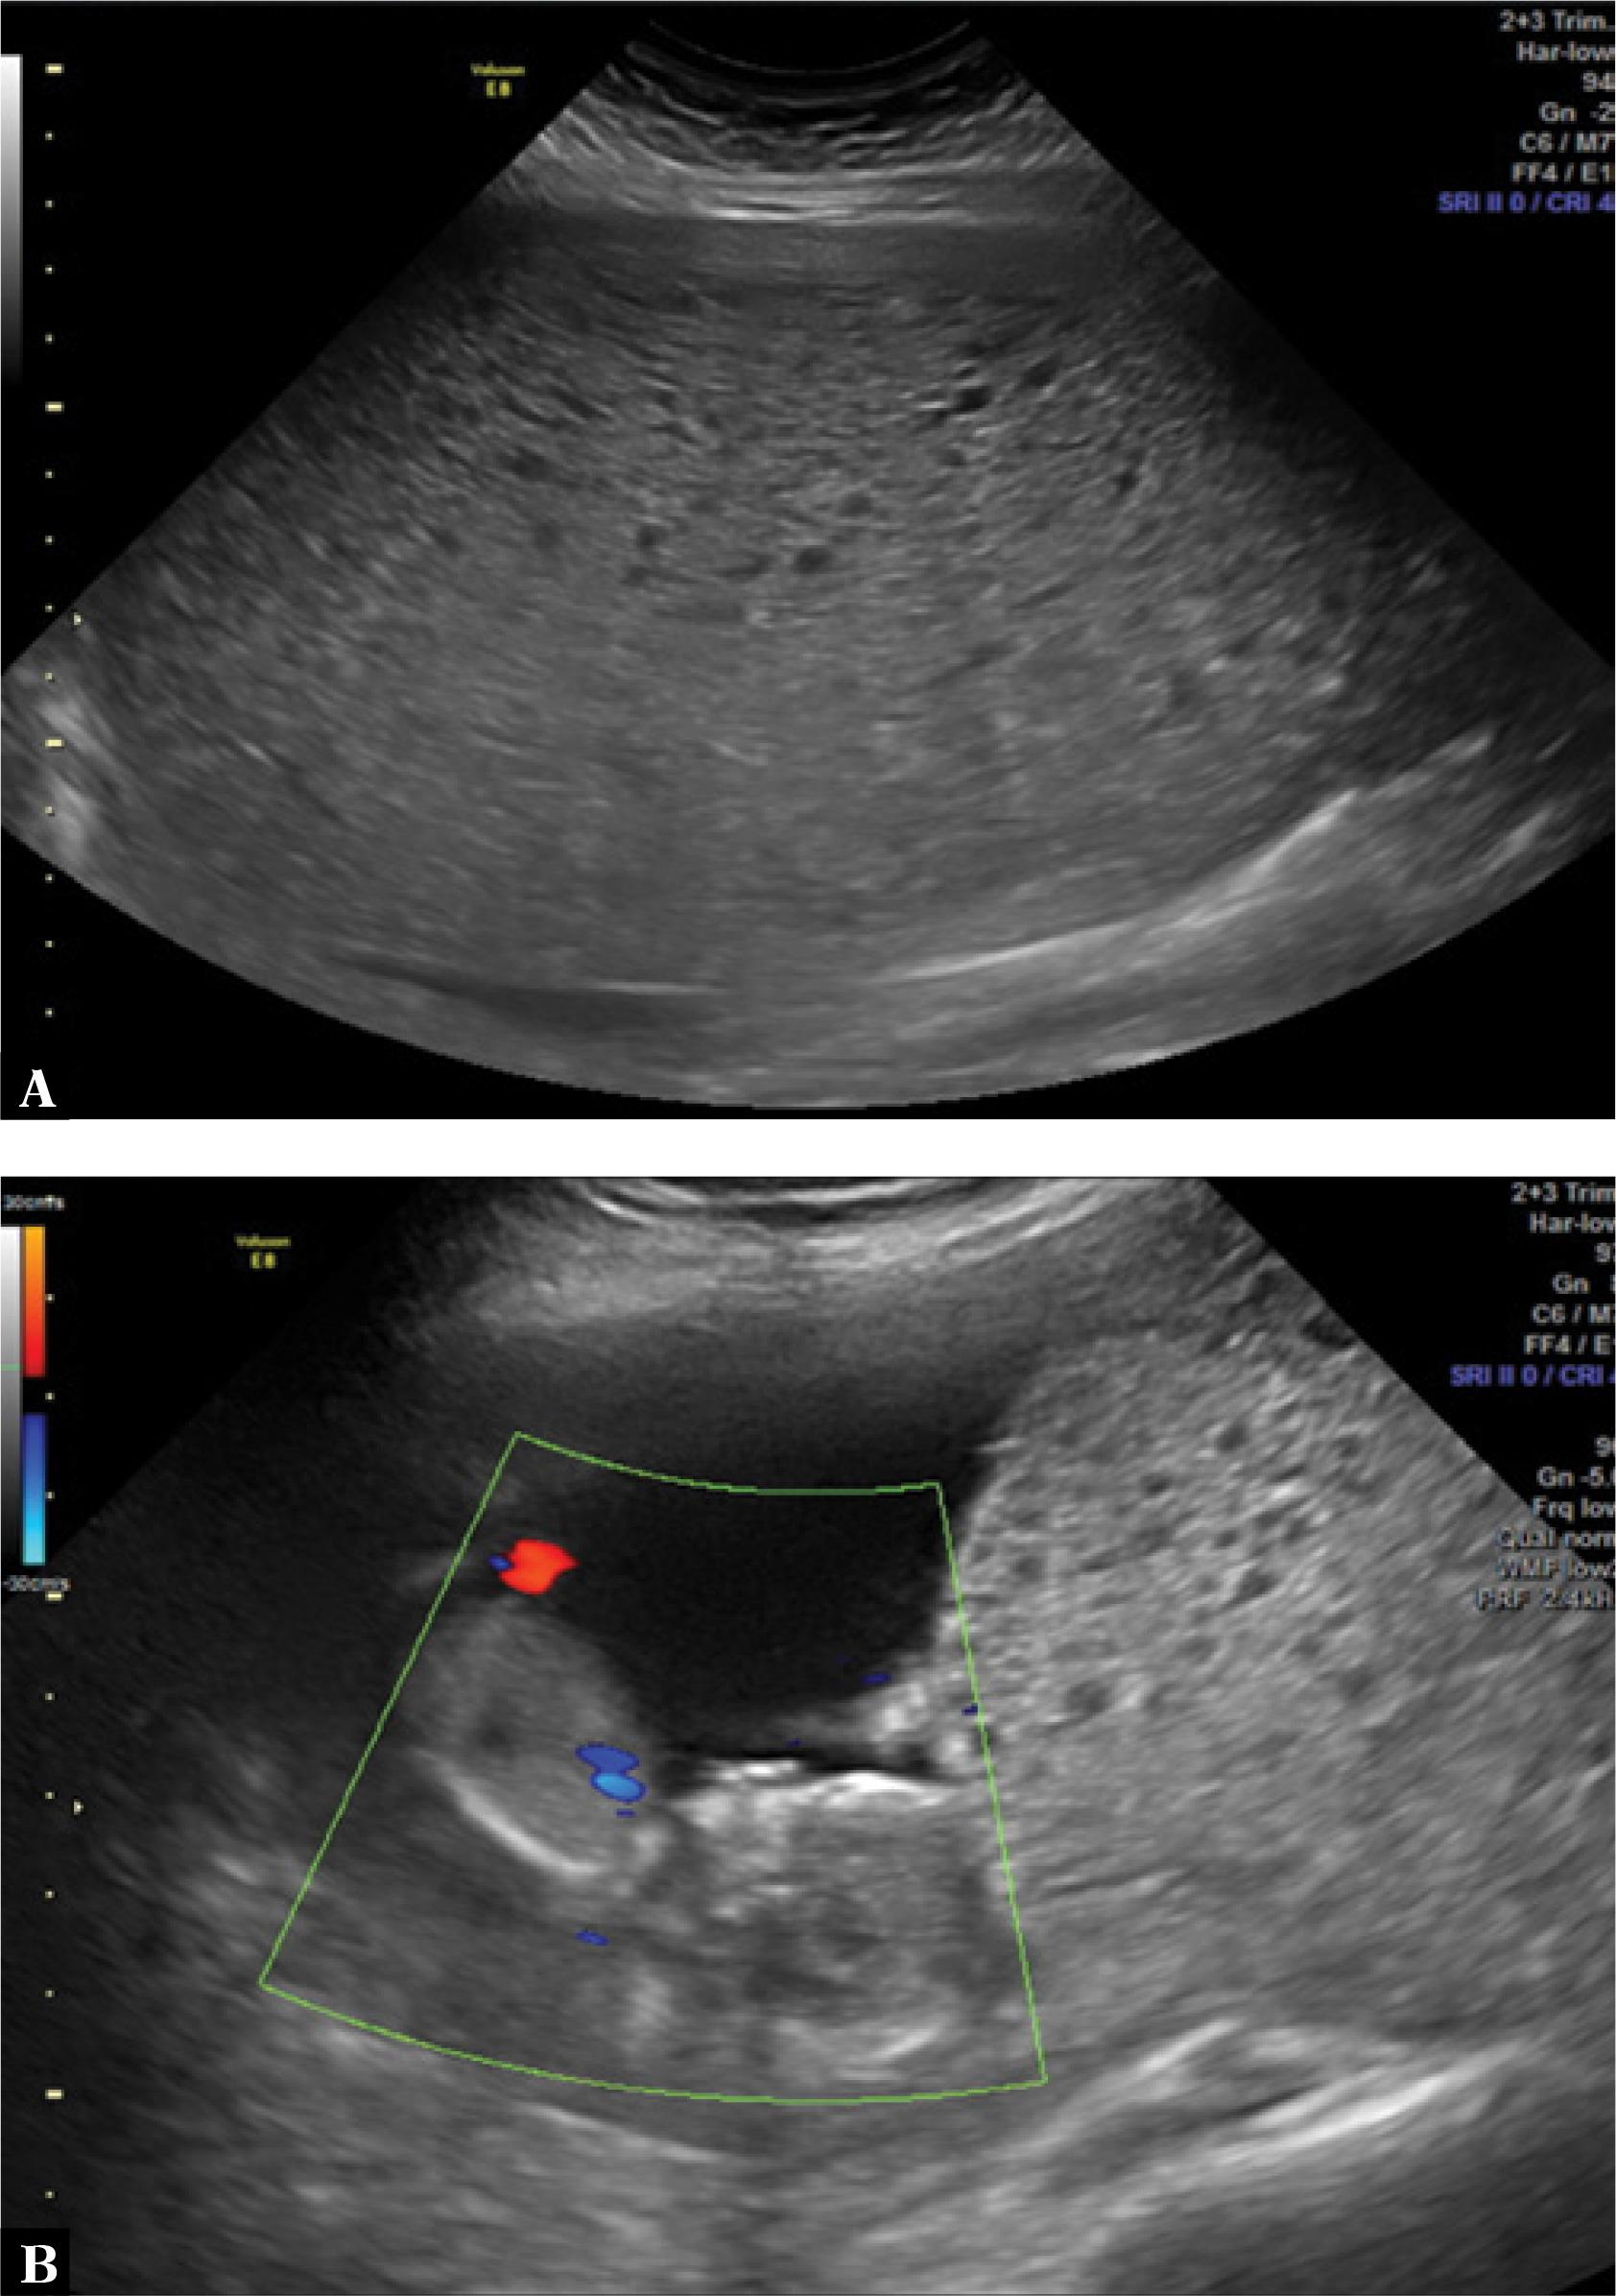

The patient complained of pelvic pain, uncontrollable vomiting and mild transvaginal bleeding. On clinical examination the patient was pale (2+/4+), hypertensive (blood pressure of 150 × 90 mmHg) and tachycardic (heart rate of 100 bpm), with the uterine fundus enlarged for the gestational age (22 cm). The level of hCG was measured again the next day, and it was 1,881,508 IU/L. A two-dimensional (2D) ultrasound showed an enlarged uterus filled with a heterogeneous pattern and a live fetus of a gestational age compatible with 14 weeks (Fig. 1).

Fig. 1

A. A two-dimensional (2D) ultrasound scan shows a uterus filled with heterogeneous echogenic material. B. A 2D ultrasound scan with color Doppler shows a fetus of a gestational age of 14 weeks and a molar aspect of the placenta